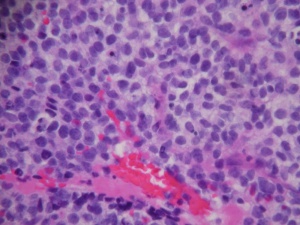

The histopathologic classification favored by the Intergroup Rhabdomyosarcoma Study divides these tumors into embryonal, alveolar, undifferentiated, and anaplastic types. By light microscopy, the embryonal subtype, which makes up 80% of orbital rhabdomyosarcomas and presents most commonly in young children (mean age 7-8), is characterized by spindle-shaped cells in various stages of differentiation (Fig. 5 and 6) with highly eosinophilic cytoplasm (Fig. 6). The alveolar subtype exhibits small, round, densely appearing cells that are loosely arranged, with septae that are similar to the alveoli of the lung. The botryoid variant of embryonal rhabdomyosarcoma, seen most commonly in infants, is defined by the presence of subepithelial aggregates of tumor cells and is named due to the common “grape-like” appearance of these cells. Immunohistochemisty is useful in identifying skeletal muscle proteins, such as alpha-actin, myosin, desmin and myoglobin. Electron microscopy can favor the diagnosis by demonstrating actin-myosin bundles or the A, I or Z band proteins, specific to muscle.

Further, cytogenetics is important in the diagnosis of RMS and differentiation between alveolar and embryonal variants. Alveolar RMS is distinguished from Embryonal RMS by the presence of one or two recurrent chromosomal translocations including t(2;13)(q35;q14) and t(1;13)(p36;q14). Embryonal RMS does not have recurrent structural chromosomal rearrangements but rather has frequent chromosomal gains and losses. In particular, there is a higher frequency of loss of one or two alleles often at chromosome 11 loci particularly in the 11p15.5 region.[5][2]